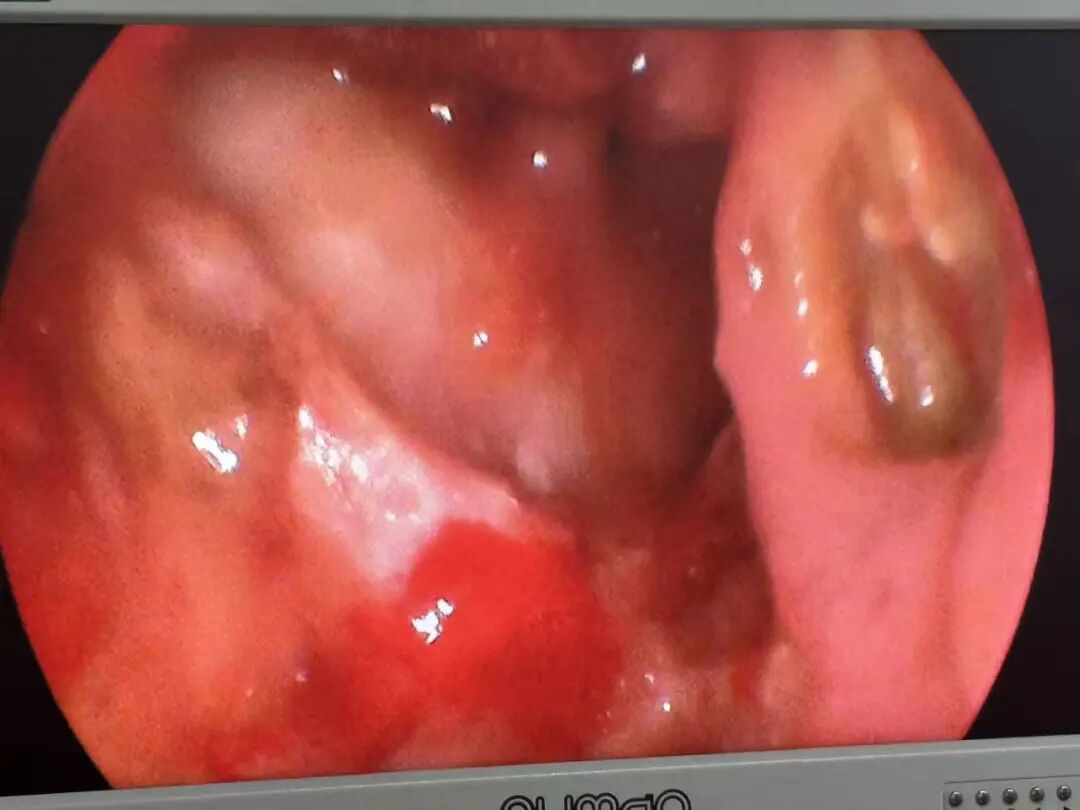

图片

手术由陆训彪主任与王振霖教授同台实施。在高清鼻内镜放大视野下,采用Draff Ⅱb术式精细处理额窦病灶,完整剥离眶内肿瘤,并完好保护受压的内直肌。针对侵犯颅底骨质的肿瘤部分,借助微型磨钻进行精细打磨,直至颅底骨质恢复平整。整台手术出血仅约10毫升,无任何神经、血管及眼球相关副损伤,真正实现了病灶全切与功能结构保全的双重目标。